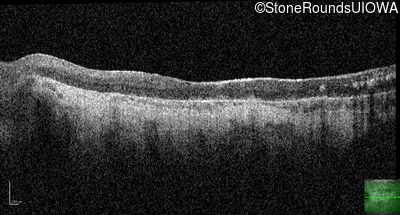

AR Stargardt Disease (IIA)

OS

Light Perception

OD

OCT Stack

AR Stargardt Disease

ABCA4

Gln636Stop CAG>TAG

His1406 del1caC

AR